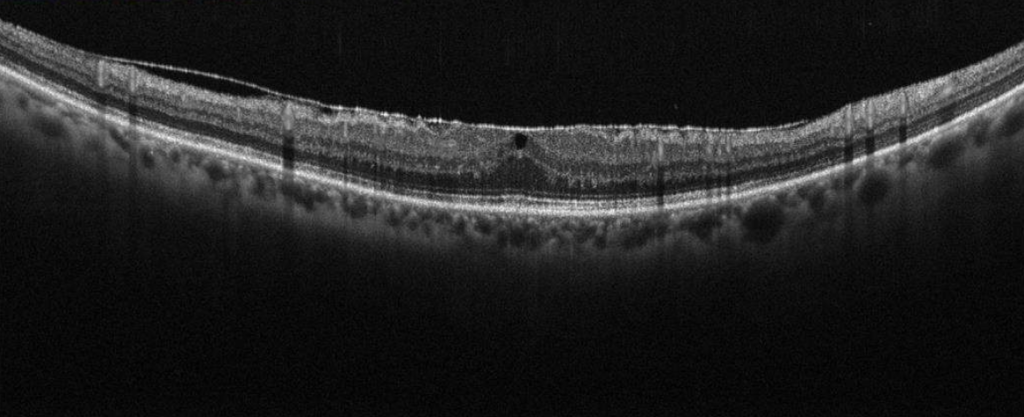

Tecnología avanzada para evaluar la retina y estructuras oculares, permitiendo detectar enfermedades.